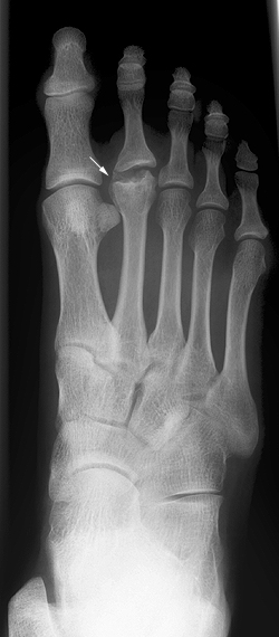

What bone is affected in Freiberg’s disease?

Metatarsal head, usually 2nd (80%), sometimes 3rd.

Who is most affected by Freiberg’s disease?

Teen females (5:1), athletes, high-heel wearers.

Pathogenesis of Freiberg’s disease?

Repeated stress → microfractures at growth plate → necrosis → deformity.

Symptoms of Freiberg’s disease?

Localized forefoot pain, tenderness, worsens with activity.

Radiographic appearance of Freiberg’s disease?

Early: cortex collapse, sclerosis, altered joint space. Late: enlarged, fragmented head.

Treatments for Freiberg’s disease?

Reduced activity, casting, or surgery (excision, transplant).